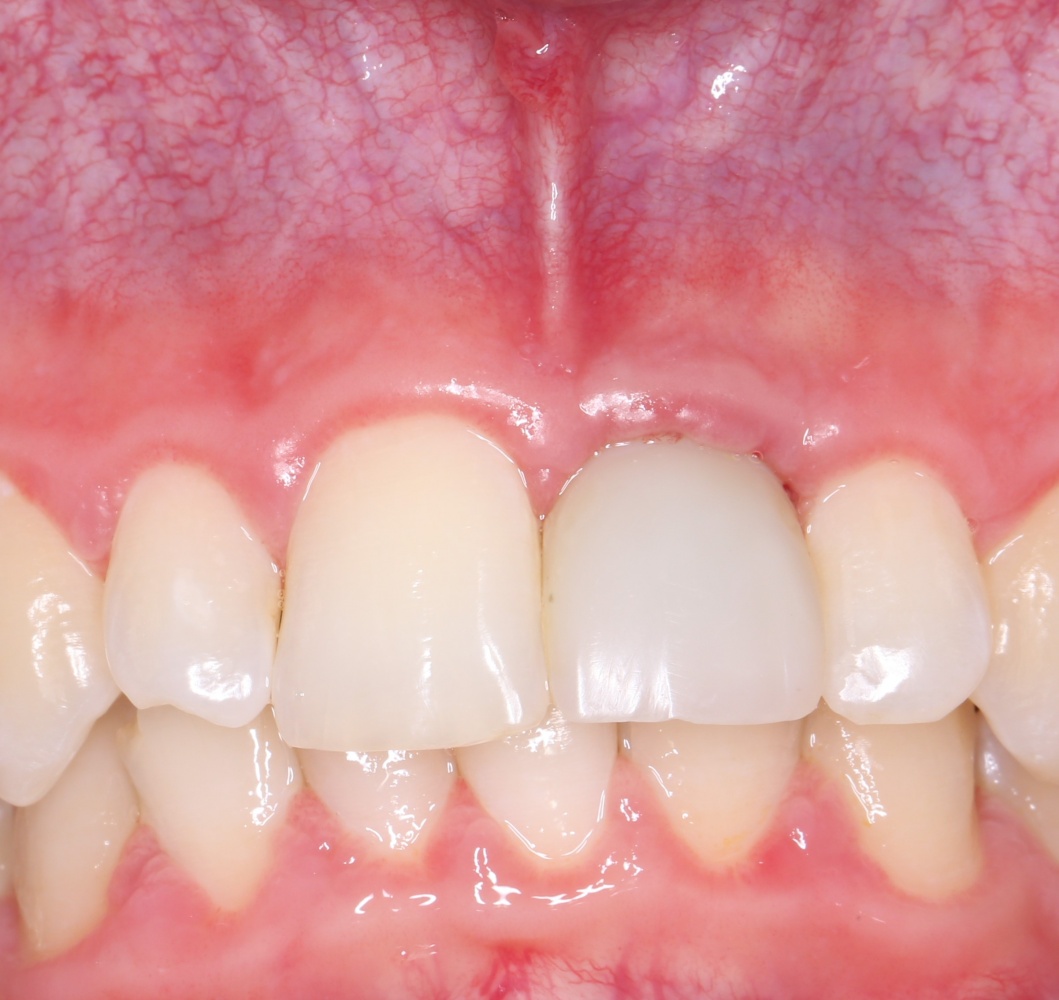

К счастью, уже через 6 недель после операции вдруг выяснилось, что ничего исправлять не нужно:

Фактически, нам осталось лишь дождаться приемлемого уровня остеоинтеграции имплантатов,  — примерно 2-3 месяца, — и можно переходить к постоянному протезированию.

Через три месяца мы сняли коронки с имплантатов, чтобы оценить качество формирования десневого контура:

С этого момента можно перестать переживать — десневой контур сформировался правильно, мы получили достаточный объём и качество окружающей платформу имплантата десны. Можно приступать к изготовлению постоянной протетики. Подрядчиком стала зуботехническая лаборатория French Creative, одна из топовых лабораторий Москвы.